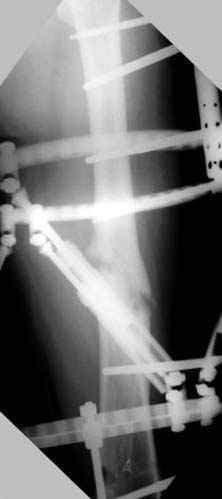

Отправитель: Alexander Chelnokov 23 Ноябрь 2004, 02:31

Если, например, доводится лечить больных с псевдартрозами шейки бедра, то надобность есть, и приходится. См. приложение.

Несколько снимков из моей коллекции, чтобы разьяснить, почему мы до сих пор делаем различные варианты остеотомии.

На рисунке N1 предоперационный план лечения ложного сустава шейки бедра- линия ложного сустава, угол и направление введения импланта, клиновидная остеотомия в градусах и миллиметрах, второй снимок после коррекции, расчет, на сколько удлиняется конечность и размеры импланта;

N3 рисунок окончательный снимок, после операции моя рентгенограмма должен выглядеть примерно как эта картина. На N4 снимке клин перед удалением; N5 послеоперации 3 нед.; N6 окончательная рентгенограмма.

(доложен в Ст. Петербурге 2003 и в Москве 2004)

варус при проксимальном отделе 95 градусной пластиной.

Отправитель: Djoldas Kuldjanov 23 Ноябрь 2004, 18:21

пластическая модель; и коррекция бедра аппаратом Илизарова.

Имею другие снимки тоже, получится как отчет о моей работе.